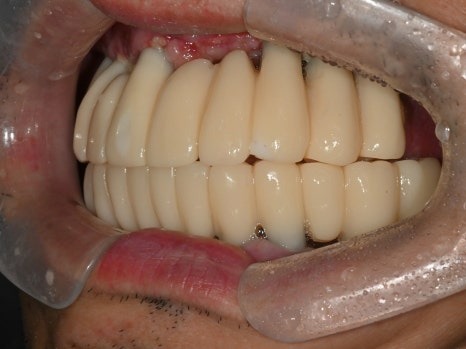

수술 2일 후

월요일에 임플란트 즉시 기능 치아(임시치아)를 끼워드렸습니다.

수술 2일후

수술 2일 만에 고정된 치아가 완성되자

놀라워하시면서 식사가 가능하게 된 걸

너무 좋아하셨습니다.